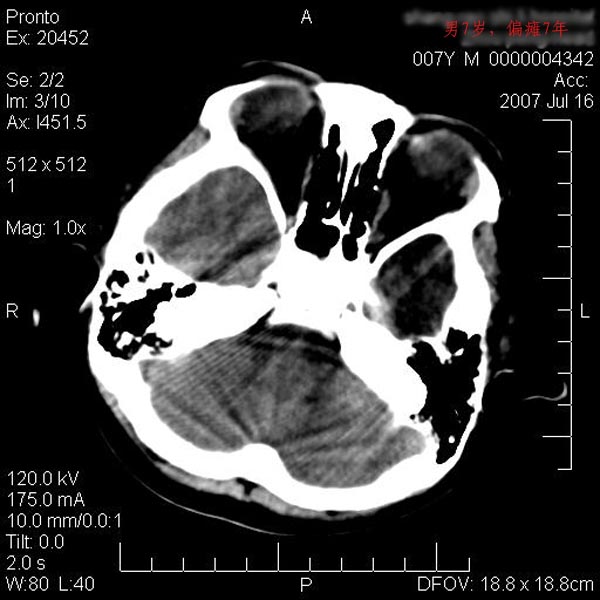

男性 7岁:偏瘫7年,出生时脑内出血。

左侧大脑半球发育不良、软化灶伴穿通畸形形成。

左侧脑叶体积缩小。密度减低,左侧脑室牵拉扩大并向左移位,左侧脑室颞角与侧裂池相通并呈囊性扩张。考虑左侧大脑发育不全,软化灶并穿通畸形。

左侧颅腔变小,左侧大脑半球体积缩小密度减低,呈负占位效应,左侧侧脑室扩大,出生时有脑出血病史。多考虑先天因素,左侧大脑前、中动脉起始部狭窄或闭塞,即烟雾病可能性大。